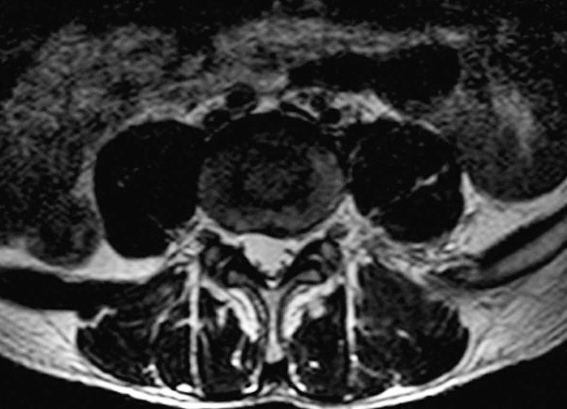

MRI轴位片:了解有无后位结肠(图8)。

图8 MRI轴位片了解有无后位结肠